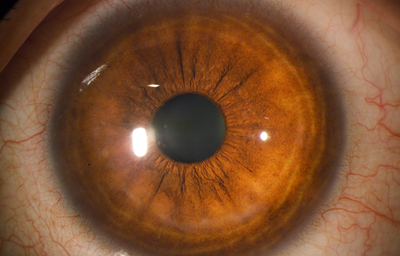

El Color del Iris

El Iris en general es muy pigmentado con colores que comúnmente van del marrón, avellana, gris, verde y azul. Existen los iris sin pigmento en el Albinismo oculo-cutáneo en cuyo caso se ven blanco/rosados.

El color del Iris es un fenómeno complejo por efectos combinados por la textura, la pigmentación y el tejido fibrovascular del estroma, junto con la constitución epigenética del individuo. Desde el punto de vista óptico, la simple absorción o reflexión selectiva por algunas moléculas, como la hemoglobina o el colágeno del estroma que son componentes no pigmentados, puede tener influencia en el color que es observado.

A pesar de la gran variedad en el color del Iris, el único pigmento que contribuye en forma sustancial es la melanina; su cantidad, es uno de los factores que determina el color del iris en una persona. Estructuralmente el color depende de la cantidad variable de eumelanina (melaninas marron/negra) y pheomelanina (melaninas rojo/amarillo) producidas por los melanocitos derivados de la Cresta Neural. El grado de dispersión de la melanina que yace en racimos subcelulares en los melanosomas, tiene cierta influencia en el color que se observa, pero el grado de dispersión no es reversible ya que los melanosomas no son moviles.

En el recién nacido el Iris es de color gris azulado por falta de migración del pigmento, el color definitivo se muestra alrededor de los 6 meses de edad.